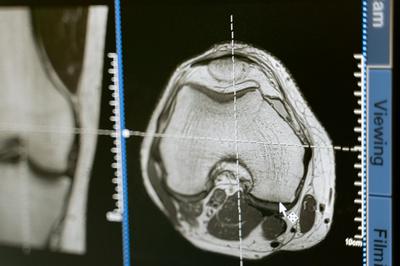

건강검진은 단순히 현재의 건강 상태를 확인하는 것을 넘어, 앞으로 발생할 수 있는 질병을 예방하고 건강한 삶을 유지하도록 돕는 중요한 역할을 합니다. 특히 한국인의 주요 사망 원인인 암, 심뇌혈관 질환 등은 조기에 발견하면 치료 성공률을 높일 수 있습니다.